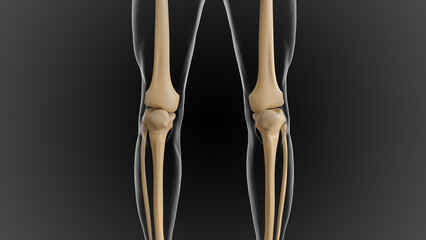

Podobny obraz Medical Elbow Anterior View X-Ray Radiograph Illustrating...